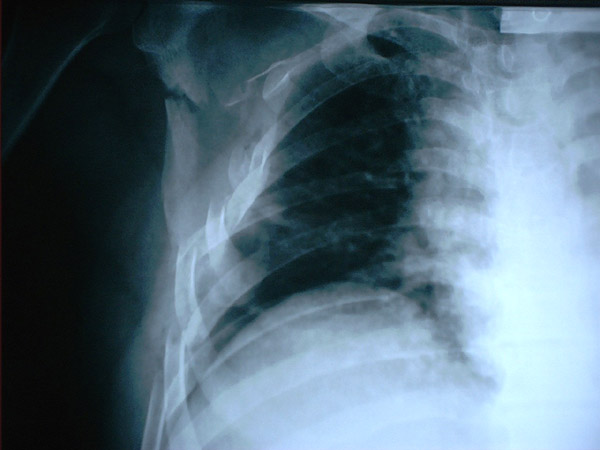

MO Fractura de omóplato y de costillas 2 a 8 derechas. Accidente de tráfico con moto en paciente centenaria. 1